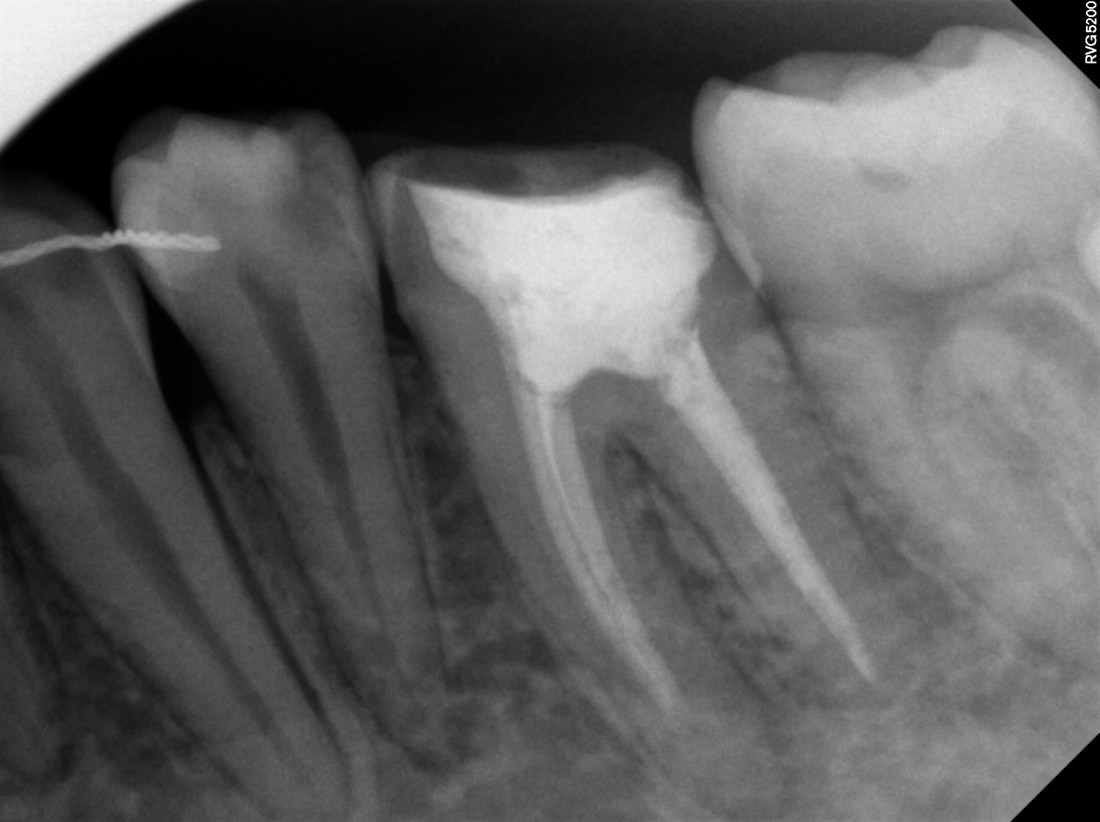

광주 성인 교정치과에서

충치치료와 교정진료를 동시에 받으신

성인 여성 환자분의 케이스입니다.

충치치료 전에는 은색 보철물이 있던 자리에

교정진료의 마무리와 동시에

치아색 보철물을 씌워서

치아교정 + 충치치료를 동시에 진행하였습니다.

광주 성인 치아교정의 경우

충치치료의 시기를 잘 판단하여

성공적인 진료를 완성할 수 있기 때문에

분과별 전문의가 협진하는

광주 성인 교정치과를 선택하시는 것이 좋습니다.